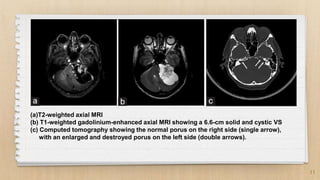

Vestibular schwannoma (acoustic neuroma) surgical anatomy and ...